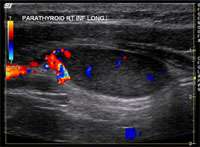

Most commonly, one of the four parathyroid glands have enlarged. However, it is possible to have two enlarged glands, or even mild growth of all 4 glands. Proper imaging tests help create a roadmap for a successful surgery. We routinely obtain multiple tests. Imaging of the parathyroid glands is challenging and sometimes the abnormal gland is not definitively seen by one or more imaging tests. That is because a normal parathyroid gland is the size of a grain of rice, and an abnormal gland may be the size of a green pea. Imaging is usually a combination of the following:

- Neck ultrasound, performed by the endocrine surgeon during the office visit

- Parathyroid 4D CT scan

- Sestamibi scan or SPECT (single proton emission computerized tomography) scan